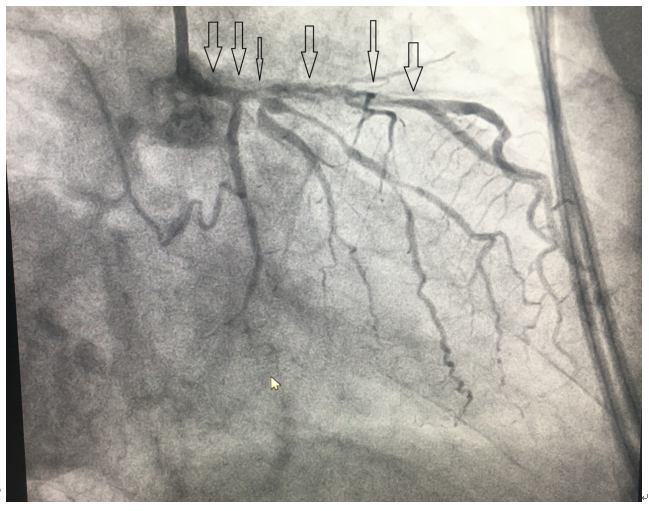

80岁胡大爷,因“活动后心累、气紧1+年,加重1周”收治心血管内科,药物治疗无好转。科内组织讨论,2月24日在数字化血管造影机下行冠脉造影,发现“左主干全程钙化,中段重度狭窄,狭窄50-60%;前降支近段及中段重度狭窄伴重度钙化,最狭窄90%-95%;中间支弥漫性重度狭窄”。

(一)造影结果